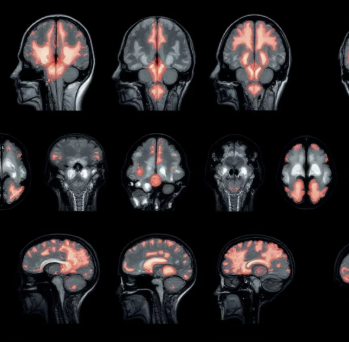

뇌졸중은 뇌에 혈액을 공급하는 혈관이 막히거나(뇌경색) 터져서(뇌출혈), 뇌의 일부가 손상되어 발생하는 질환입니다. 뇌는 산소와 포도당 공급이 단 몇 분만 중단되어도 손상되기 시작하며, 손상된 뇌 영역이 담당하는 신체 기능(운동, 언어, 감각 등)에 갑작스럽게 장애가 발생합니다.

단계 영어 약자 증상 확인 조치 1 Face (얼굴) 웃어보라고 했을 때, 한쪽 얼굴이 처지는가? 확인 2 Arms (팔) 양팔을 앞으로 들었을 때, 한쪽 팔이 떨어지는가? 확인 3 Speech (말) 간단한 문장을 말하게 했을 때, 말이 어눌하거나 이상한가? 확인 4 Time (시간) 위 증상 중 하나라도 나타났다면 증상 발생 시각을 확인하고 즉시 119에 전화하세요! 즉시 119 신고! 응급실에서의 초기 치료: 병원에 도착하면 곧바로 CT 또는 MRI 촬영을 통해 출혈인지 경색인지 진단합니다. 진단 결과 뇌경색이며 골든타임 이내라면 혈전을 녹이는 약물(tPA)을 투여하거나, 막힌 혈관을 직접 뚫는 기계적 혈전 제거술을 시행하여 뇌졸중으로 인한 뇌 손상을 최소화합니다.